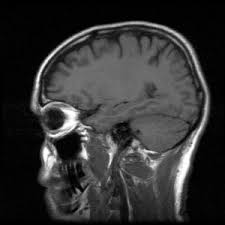

A memória korai hanyatlása a legújabb kutatások szerint a későbbi demencia első jele lehet, ami már 45 éves korban elkezdődhet.

Az eddigi véleményekkel szemben, miszerint a mentális hanyatlás csak 60 éves kor után kezdődik, a legújabb kutatásokból kiderült, hogy már jóval korábban, 45 éves korban is beindulhat. Az első jelei a memória hanyatlása, valamint az érveléssel és megértéssel kapcsolatos problémák.

A kutatók szerint ezek az eredmények összefüggésben vannak az egészséges életmóddal, hiszen ahogy fogalmaztak "ami jó a szívnek, az jó az agynak is". Vagyis a mozgásszegény életmód, a helytelen táplálkozás és az elhízás, nem csak szív- és érrendszeri betegségeket okozhat, hanem hozzájárulhat a korai mentális hanyatláshoz is. Singh-Manoux azonban hozzátette, hogy fontos megjegyezni, a kognitív változásokkal járó öregedés nagyon különbözik a kognitív változásokkal járó Alzheimer-kór folyamataitól.